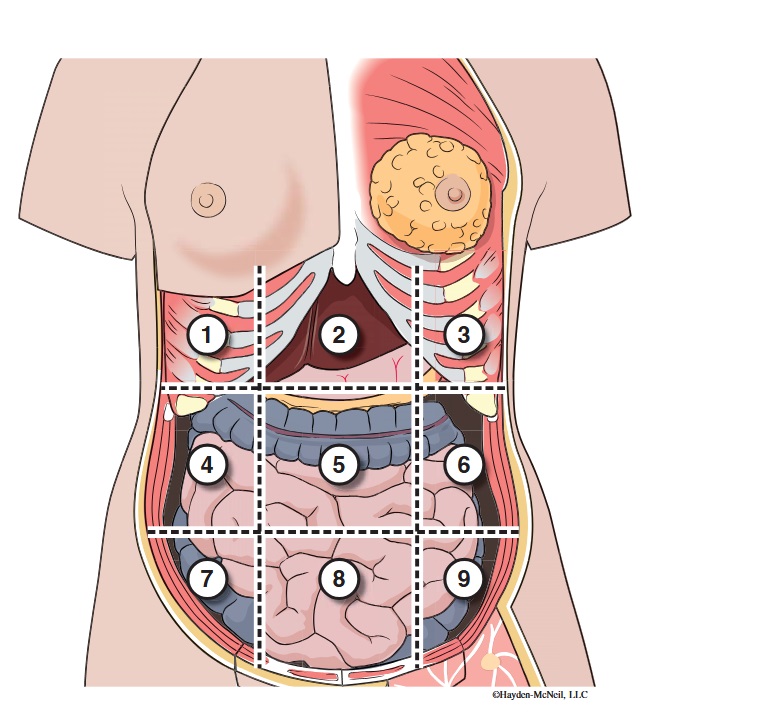

What abdominal region is labeled #1?

right hypochondriac

What abdominal region is labeled #2?

epigastric

What abdominal region is labeled #3?

left hypochondriac

What abdominal region is labeled #4?

right lumbar

What abdominal region is labeled #5?

umbilical

What abdominal region is labeled #6?

left lumbar

What abdominal region is labeled #7?

right iliac/ inguinal

What abdominal region is labeled #8?

hypogastric

What abdominal region is labeled #9?

left illiac/ inguinal

What organs are apart of the right hypochrondriac region?

right lobe of liver, gallbladder, right adrenal gland

What organs are apart of the epigastric region?

pyloric end of stomach, duodenum, pancreas

What organs are apart of the left hypochondriac region?

stomach, spleen, left adrenal gland

What organs are apart of the right lumbar region?

ascending colon, right kidney, portion of small intestine

What organs are apart of the umbilical region?

omentum, mesentery, small intestine

What organs are apart of the left lumbar region?

descending colon, left kidney, portion of the small intestine

What organs are apart of the right iliac/ inguinal region?

cecum of large intestines, appendix, right ovary

What organs are apart of the hypogastric region?

ileum, bladder, uterus

What organs are apart of the left iliac/ inguinal region?

sigmoid colon, left ureter, left ovary